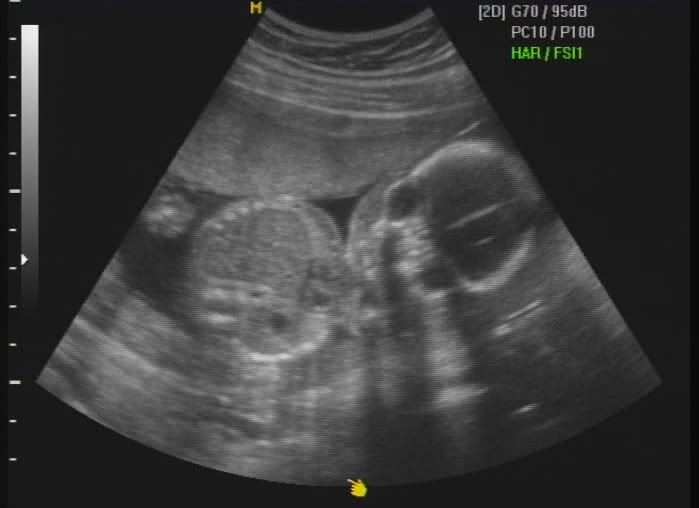

Hola a todos!, me presentaría, pero todavia no he nacido y no tengo nombre, se supone que lo haré aproximadamente el 26 de Marzo, mis papis (Dinís y Bárbara) acaban de enterarse de que voy a ser una niñita y están pensando en que nombre ponerme, a ellos les gustaría un nombre compuesto ya que es tradición en sus dos familias, pero como tienen un lio del carajo he decidido abrir este blog primero para que les ayudeis con mi nombre, y después para que sigais mi evolución como bebecita.